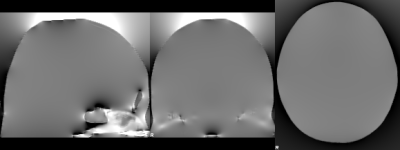

B0 inhomogeneities occur at interfaces of materials with different magnetic susceptibilities, such as tissue-air interfaces. These differences lead to distortion in the local magnetic field, as Maxwell’s equations need to be satisfied (an example of the distorted field is shown in the image to the right).